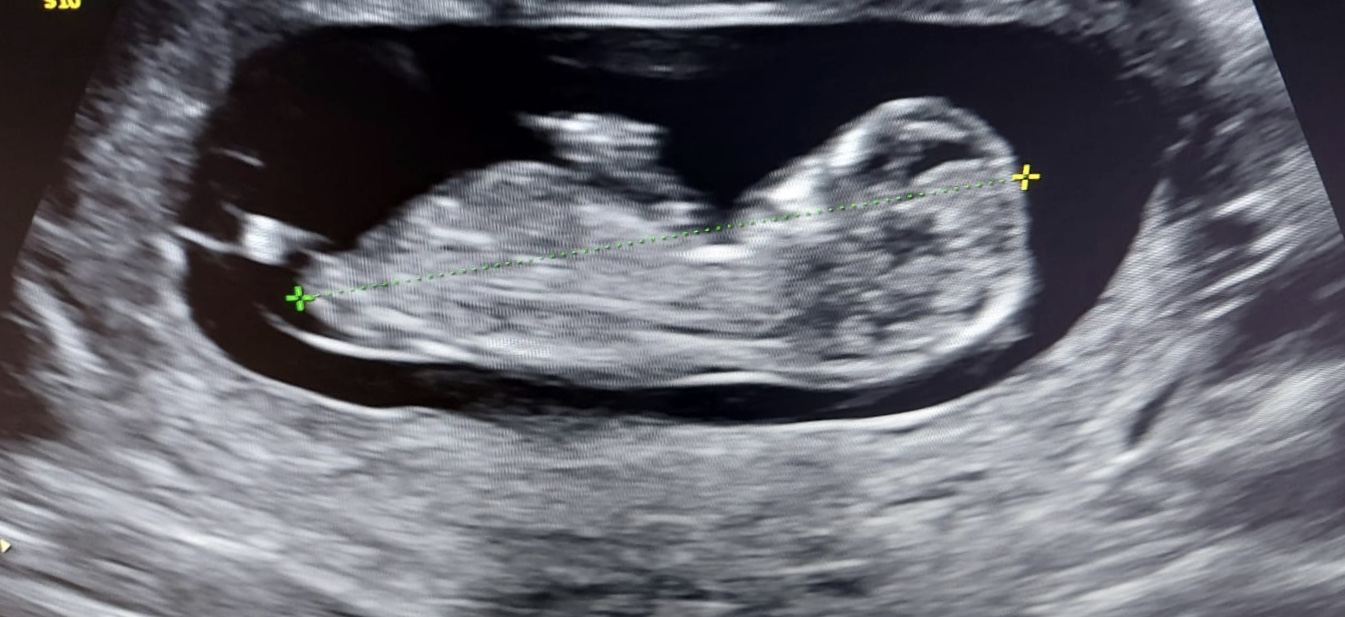

Benim bebeğime de bakar mısınız 12 hafta 3 günlük

209,5 KB · Görüntüleme: 457

136,1 KB · Görüntüleme: 1.325